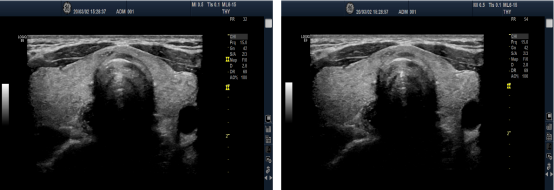

D* x8 U& f& }% Z1 ?0 \5 |0 [ M型模型

3 h) \2 \; e5 p M型可调参数中最重要的是总增益、时间增益补偿(TGC)以及扫描速度。M型最主要的价值是时间分辨率,它可以加强对快速移动物体的展示 。高达100~200 mm/s的扫描速度对获取最准确的时间相关的测量值是十分有利。而低速扫描则适于观测多次心跳。M型可以描绘最佳的心动周期内某结构的运动时间 。 + Q3 t7 M, t8 m/ B4 C( q k: s" Y

1

0 H, Z- e; a8 H4 ?1 b 彩色M型

$ A* J; d0 ?5 n, m 彩色M型结合了CDI取样和M型追踪。它可通过明显增加血流活动的瞬时分辨率来帮助测定心动周期内某彩色血流活动的时间。例如,这项技术可为心动周期内喷射不足时,评估流入左室(LV)血液传输速度。

0 m4 S5 g* c( \ 2

$ d5 e, t! c) C4 L& N! V 解剖M型(AMM)

7 T* N6 z* Q5 n: ?! a( F 对ROI进行倾斜取样时,线型测量被高估。对于某些具有“陡峭”心脏的患者,解剖M型可使取样线指向垂直于ROI的方向转动,而非保持在2D图像扇区中心固定的原点。这可有针对性地提高具有“陡峭”心脏或轴偏离患者的M型测量准确度。注意,此图像瞬时和距离分辨率都劣于2D图像的参数,与直接获取的M型图像相差很多。